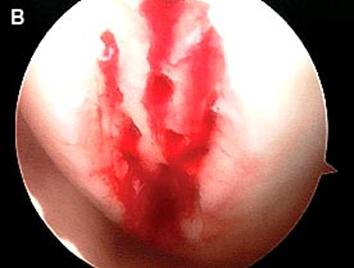

Fig.28.

Sange din microfracturi.

Artroscopia arata repararea tesuturilor la sase saptamani.

Dupa indepartarea cu succes a stratului de cartilaj calcifiat, o andrea este folosita pentru a face mai multe gauri mici (mirofracturi) in osul expus al defectului condral aflate la distanta de 1-2 mm. Trebuie lasata o punte de oase potrivita intre gauri. Tehnica de microfracturi are numeroase avantaje fata de foraj. Mai intai de toate, creaza o leziune termala mai mica. Mai mult, cu microfracturi, chirurgul este capabil sa intre in zonele dificile ale suprafetei articulare cu un control mai bun asupra adancimii de patrundere. La finalizarea microfracturii, o suprafata aspra este generata pentru a aderenta cheagului de sange care contine celule mezenchimale nediferentiate de la osul subcondral. Trebuie avut grija ca cele mai marginase parti ale leziuni sa fie patrunse de andrea pentru a ajuta la vindecarea tesutului reparator la imprejmuirea suprafetei articulare. Odata ce microfractura este finalizata, pompa artroscopica este oprita pentru a se asigura ca sangerarea maduvei curge din gaurile mici umpland defectul.[54]